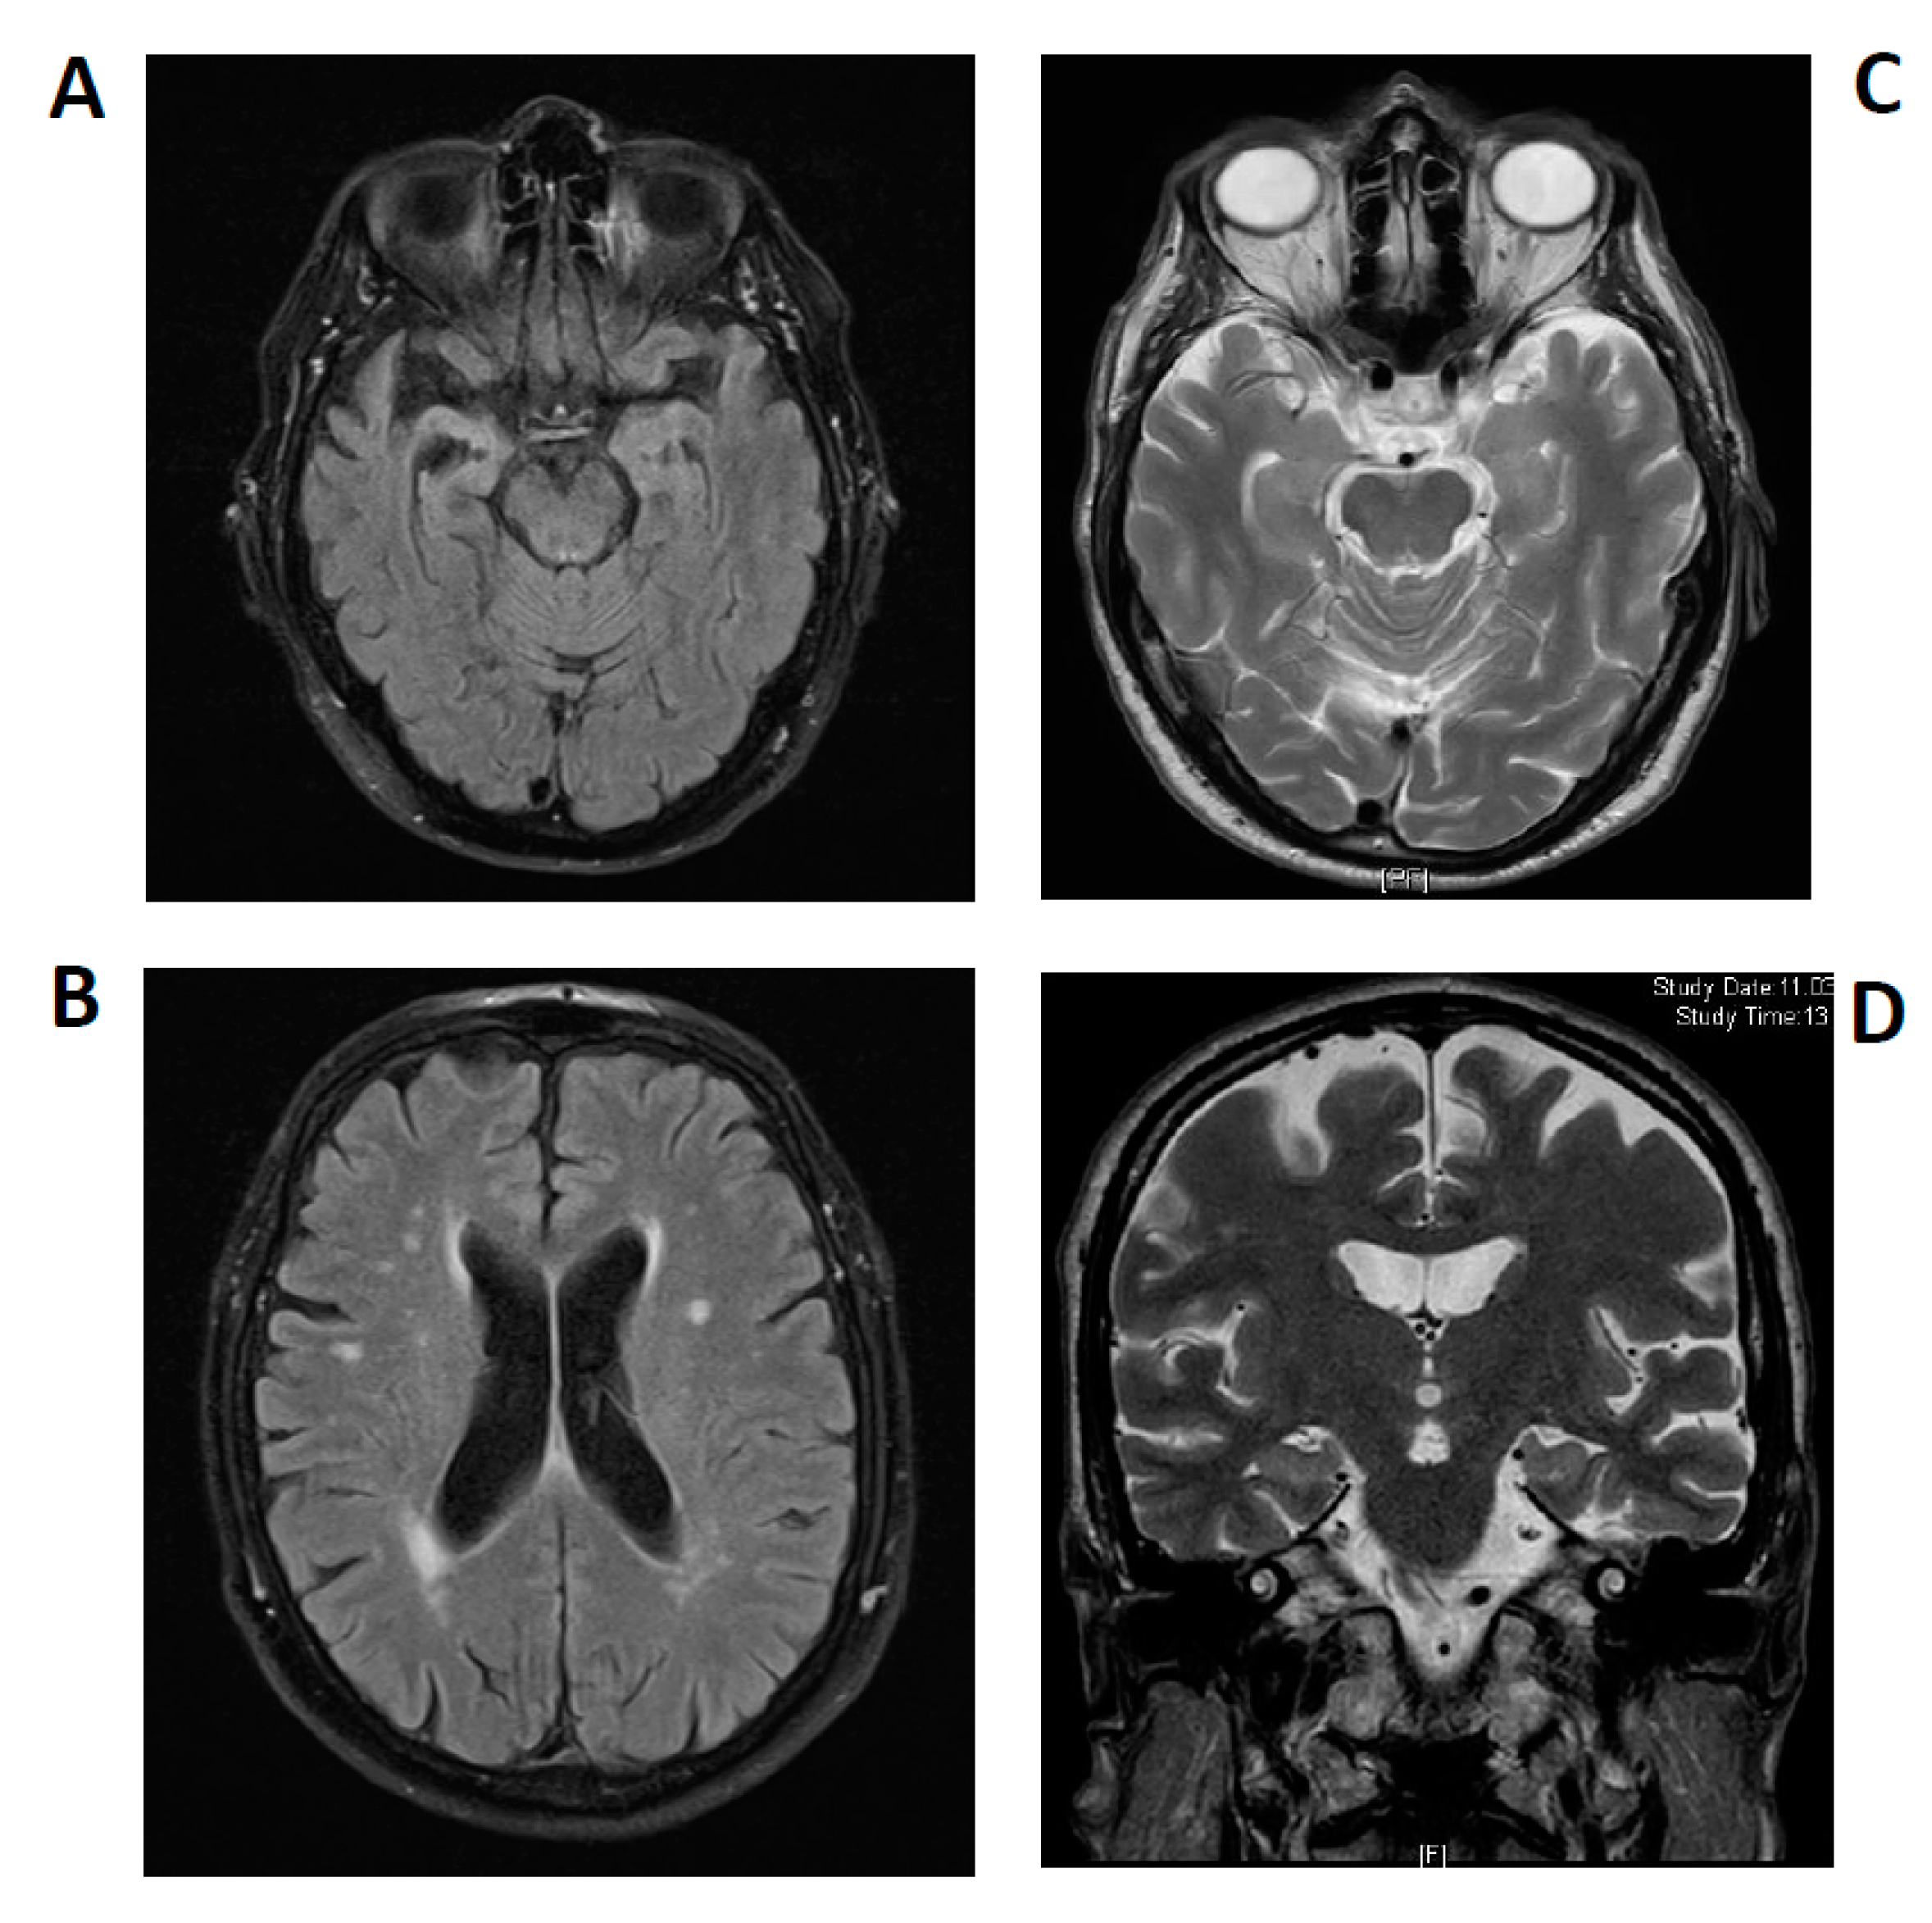

2.1. Case 1

2.2. Case 2